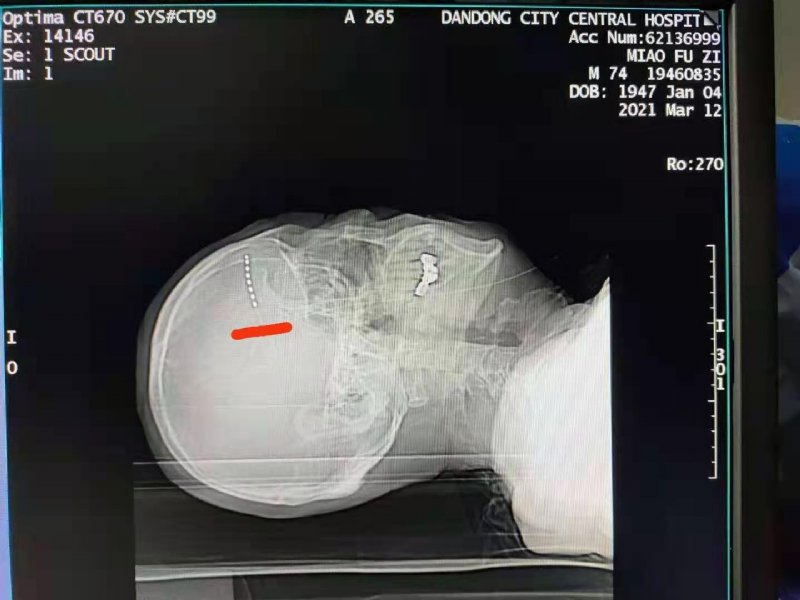

近日我院疼痛科为一位饱受带状疱疹后神经痛困扰的患者进行了周围神经电刺激镇痛术。患者右上额部带状疱疹后遗疼痛一年半,并导致右眼失明,疼痛夜间加重,多方求医效果不佳,患者痛苦不堪。收入我院疼痛科后,给予行周围神经电刺激镇痛术。术后疼痛立即缓解,让患者重拾了生活的信心。

周围神经电刺激镇痛术是用电极经皮穿刺神经或开放性手术将电极放置在神经干表面,然后采用导线连接刺激器进行电刺激,利用疼痛的闸门学说为理论基础,通过植入的电极传递的电刺激,阻断疼痛信号通过脊髓向大脑传递,使疼痛信号无法到达大脑皮层,从而达到控制疼痛的目的。适用于下肢动脉粥状硬化闭塞症、糖尿病足、带状疱疹后神经痛、顽固性背痛、术后疼痛综合症等各种疑难性疼痛。带状疱疹发病率逐年增加,60岁以上老年患者带状疱疹后神经痛发生率高达50%--75%。随着人口的老龄化,带状疱疹和带状疱疹后神经痛的发病率会显著增加。该项技术的出现将极大的改善患者的痛苦。